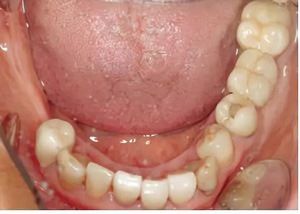

圖2-圖6:2013 年10 月15 日口內(nèi)狀況。

口外檢查未發(fā)現(xiàn)異常。牙齒和牙周狀態(tài)如圖1 和2-6所示??傮w來(lái)說(shuō),已有的修復(fù)體已不完善。第一次就診時(shí),檢查發(fā)現(xiàn)17、15、11、36、45 和46 號(hào)牙齒已缺失。16、14、12、27、37 和35 號(hào)牙齒已做過(guò)根管治療。所有剩余的牙齒牙髓活力測(cè)試均正常,叩診檢查未見(jiàn)異常。橋基牙37 已發(fā)生大面積的繼發(fā)齲,33 號(hào)牙齒齲壞和43 號(hào)牙齒繼發(fā)齲。16 和14 號(hào)牙齒根管充填不足且有根尖周炎。35 號(hào)牙齒的根管充填似乎是邊緣封閉、無(wú)氣泡,但也欠充。所有需要保留的牙齒的平均牙周附著喪失為5-6mm(最大9mm),探診深度(ST)為4-5mm(最大8mm)。27 號(hào)牙齒單獨(dú)的探診深度已達(dá)15mm。牙齦緣普遍松軟,下頜前牙舌側(cè)區(qū)域附著堅(jiān)硬的菌斑。整個(gè)邊緣牙齦發(fā)生炎癥性改變,特別是腭側(cè)區(qū)域。